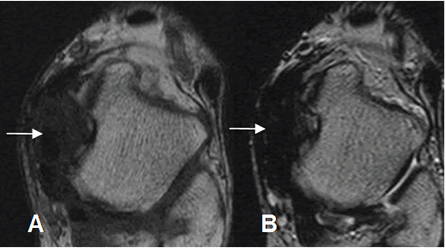

Fig 91. Pinzamiento anterior.

A: RM sagital y B: RM coronal en STIR. Edema óseo en la tibia y el talo, por el microtrauma repetido.